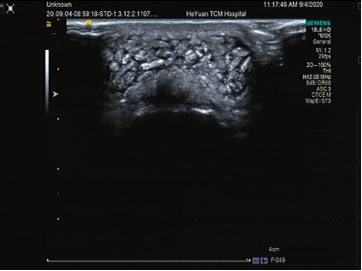

↑滑膜炎